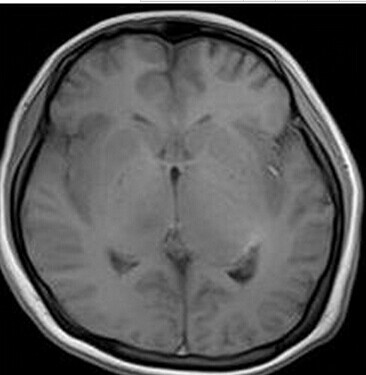

患者:女,23岁,主因嗜睡、言语不利三个月,四肢无力、吞咽障碍3个月入院。

查体:嗜睡,构音障碍,双侧掌颌反射阳性,四肢肌力Ⅳ级

【正确答案】D 大脑胶质瘤病

大脑胶质瘤病的特征性影像学表现是:

(1)肿瘤常累及2-3个脑叶,白质改变为主,占位效应不明显或轻度占位效应;

(2)病变区大脑结构相对保留;

(3)增强后多无强化。